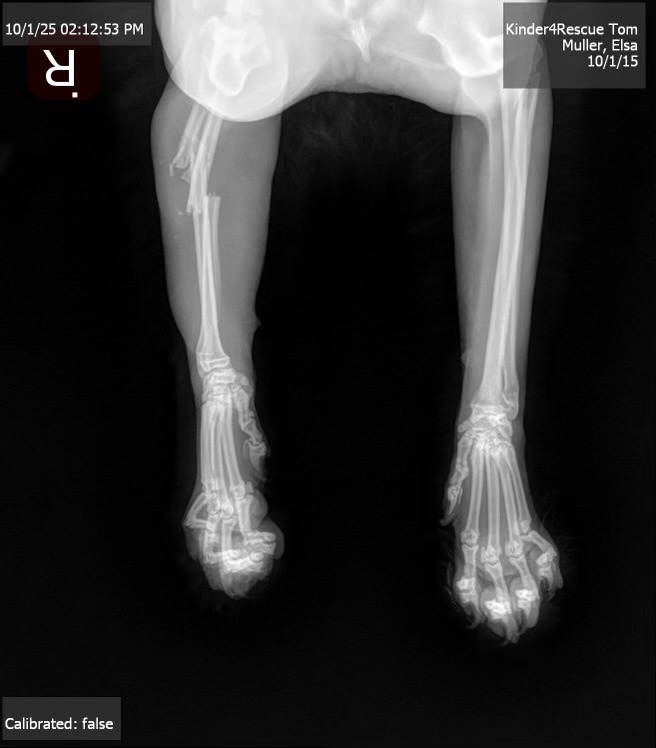

“Family and friends, my beloved Tom had an accident where a large bed frame fell on him and broke his arm. He is in a lot of pain and unfortunately needs surgery. It's going to cost an arm and a leg (no pun intended). Any amount is greatly appreciated.”